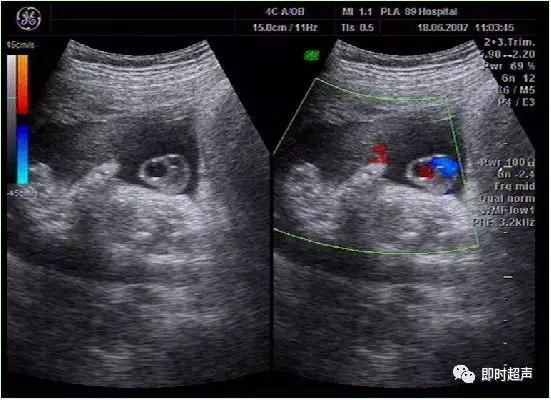

八、单脐动脉(SUA)

正常脐带内有两条脐动脉和一条脐静脉,供给胎儿营养。单脐动脉 , 指脐带内只有一条脐动脉和一条脐静脉,它是最常见的一种脐带异常。发生率约为0. 2% ~1.1%。

发生原因:可能为在脐动脉发育过程中,由于一条脐动脉发育不良或萎缩,或在早期暂时出现的单脐动脉期持续下去,都可能形成单脐动脉。

单脐动脉超声诊断

单脐动脉胎儿仅见一根脐动脉于膀胱一侧,经膀胱腹部横切面可判断左侧或右侧脐动脉缺如。羊水中脐带纵切面仅见两根血管并行或螺旋状排列, 横切时可见两个大小不一的圆环并行排列,彩色多普勒显示一红一蓝彩色血流信号。